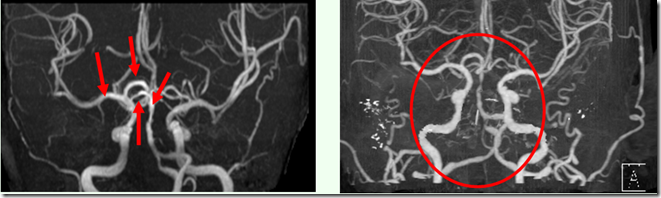

2013.01.10(四) 该部位之栓塞竟已完全消失

2013.01.07(一) 2013.01.10(四)

按推原始点前, 栓塞处清晰可见。 按推原始点后,栓塞处已消失。

2013.01.11(五) 经医院诊断脑栓塞已消除,已可出院。